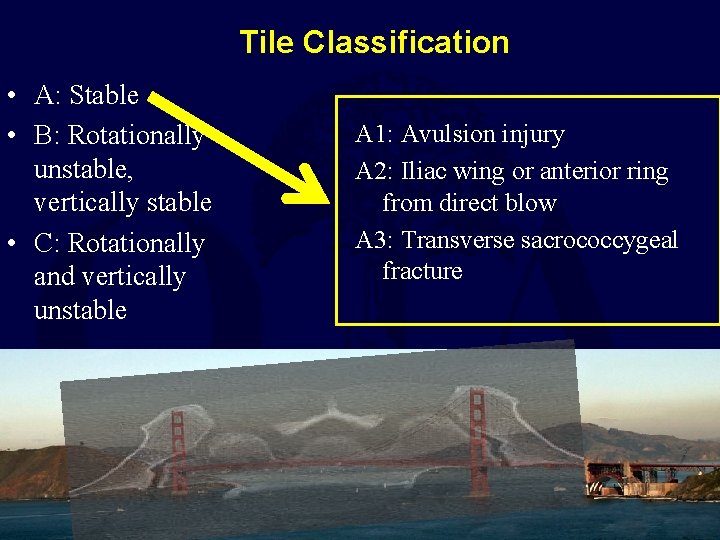

Tile Classification • A: Stable • B: Rotationally unstable, vertically stable • C: Rotationally and vertically unstable A 1: Avulsion injury A 2: Iliac wing or anterior ring from direct blow A 3: Transverse sacrococcygeal fracture